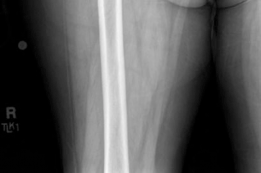

Femoral Preparation and Cementing Technique

Attention was then turned to the femur. The proximal femur was elevated and externally rotated. The femoral canal was entered using a box osteotome, taking care to lateralize the entry point into the greater trochanter to avoid varus malpositioning of the stem.

The canal was sequentially broached using a collarless, polished, double-tapered stem system. In a cemented technique, the broach size determines the size of the cement mantle, not the press-fit of the stem. A line-to-line broaching technique was used to allow for a uniform 2mm cement mantle.

Modern, third-generation cementing techniques are mandatory to ensure long-term survivorship and minimize the risk of Bone Cement Implantation Syndrome (BCIS). The steps performed included:

4. Cement Restrictor: A distal intramedullary cement restrictor (plug) was sized and inserted 1-2 cm distal to the planned tip of the stem. This prevents distal migration of the cement and allows for effective pressurization.

5. Cement Mixing and Delivery: Polymethyl methacrylate (PMMA) bone cement was mixed under vacuum to reduce porosity and increase fatigue strength. Once the cement reached the doughy phase, it was injected into the canal in a retrograde fashion using a cement gun, starting from the restrictor and withdrawing the nozzle as the canal filled.

6. Pressurization: A proximal seal was applied, and the cement was pressurized to force it into the cancellous bone micro-architecture.

7. Stem Insertion: The polished, double-tapered stem was inserted in the correct version (approximately 10-15 degrees of anteversion) and held rigidly until the cement fully polymerized.